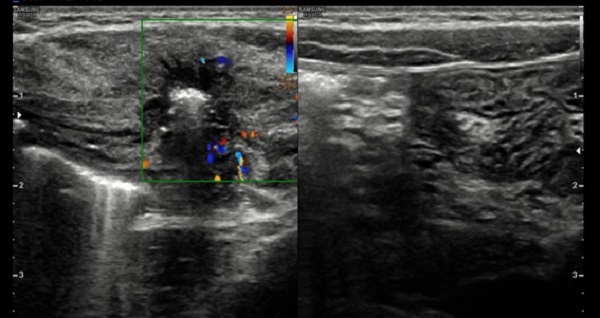

Ante la sospecha de hernia de Spiegel, se pide nueva ecografía orientada, que confirma el diagnóstico (Figs. 1 y 2).

La ecografía abdominal, prueba complementaria que confirma el diagnóstico, no está exenta de dificultades, debido a que la masa es evanescente. El interior del saco herniario puede estar vacío, pero también puede contener asas intestinales o el testículo ipsilateral, cuando se asocia a criptorquidia. La ecografía Doppler valora si hay estructuras vasculares implicadas.